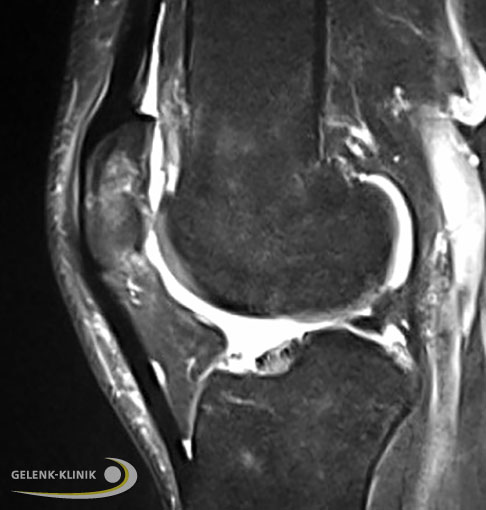

Knorpelschaden im Kniegelenk, seitlich Seitliche MRT-Aufnahme eines Knorpelschadens im Kniegelenk. Der Knorpelschaden erscheint weiss in dem ansonsten homogenen hellgrauen Bereich (gesunder Knorpel) an der Rückfläche der Kniescheibe. © Gelenk-Klinik Knorpelschaden im Kniegelenk, quer Als Folge des Knorpelschadens hat sich zusätzlich eine Flüssigkeitsansammlung im Knochen der Kniescheibe (Patella) gebildet. Das Knochenödem stellt sich als aufgehellter Bereich oben im MRT-Bild dar. © Gelenk-Klinik